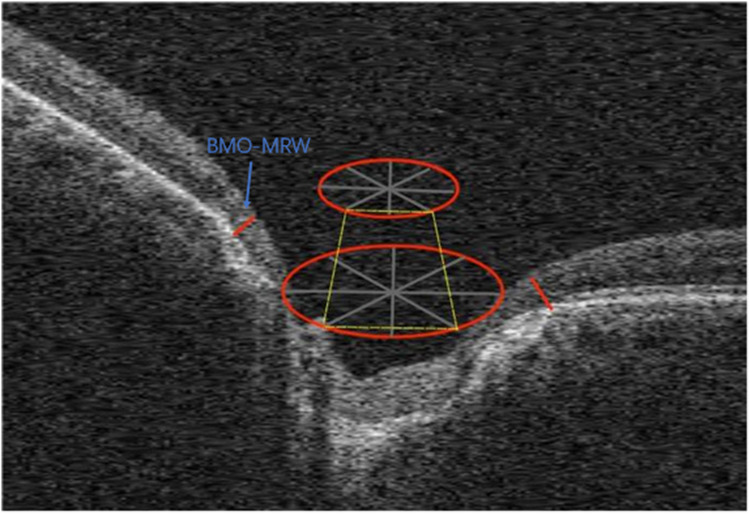

Glaucoma is the leading cause of irreversible blindness worldwide. It is an ocular disease characterized by an increase in intraocular pressure or, in some cases, normal intraocular pressure, which leads to optic nerve damage and progressive constriction of the visual field (VF). Primary Open-Angle Glaucoma (POAG) and Primary Angle-Closure Glaucoma (PACG) represent the predominant forms of glaucoma. Numerous hypotheses have been posited to elucidate the pathogenic mechanisms underlying these conditions. There is an emerging understanding of the distinct pathological processes that differentiate the various types of glaucoma. While some similarities in the mechanisms between PACG and POAG have been suggested, evidence indicates that there are also significant differences between the two. This review synthesizes the similarities and differences in the etiology of optic neuropathy caused by POAG and PACG, considering their respective pathophysiological mechanisms, the morphology of the optic disc and surrounding tissues, genetic characteristics, optical coherence tomography angiography, optical coherence tomography, and structural and functional features from VF examinations. These characteristics may contribute to a deeper comprehension of the underlying pathogenesis of glaucoma and enhance the management of different types of this ocular condition.